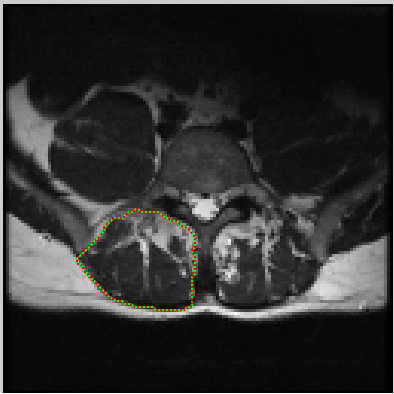

The first step is selecting the region of interest (ROI) from the MRI-defined lumbar muscles, which can be any among the erector spinae (ES) muscles, lumbar multifidus muscles (LMM) or psaos muscles, located either on the right or the left side of the spinal column [2, 5]. The user has to define the ROI by plotting a mask over the input image using livewire technique [21], as shown in Figure 2.

The livewire (or intelligent scissors) [21] is a semi-automatic image segmentation technique that allows the user to interactively select the ROI on an input image using mouse clicks along the contour of the ROI. When the user starts the selection of the ROI with a mouse click, a virtual wire is created linking the first clicked point (referred to as an anchor) to the point where the mouse is over, following a path that is as close as possible to image features detected as edges using Dijkstra’s lowest cost path algorithm. Figure 2 shows the result of a user segmentation using this tool.

Refer to caption

Figure 2: MRI input image with user defined mask using Livewire interactive segmentation